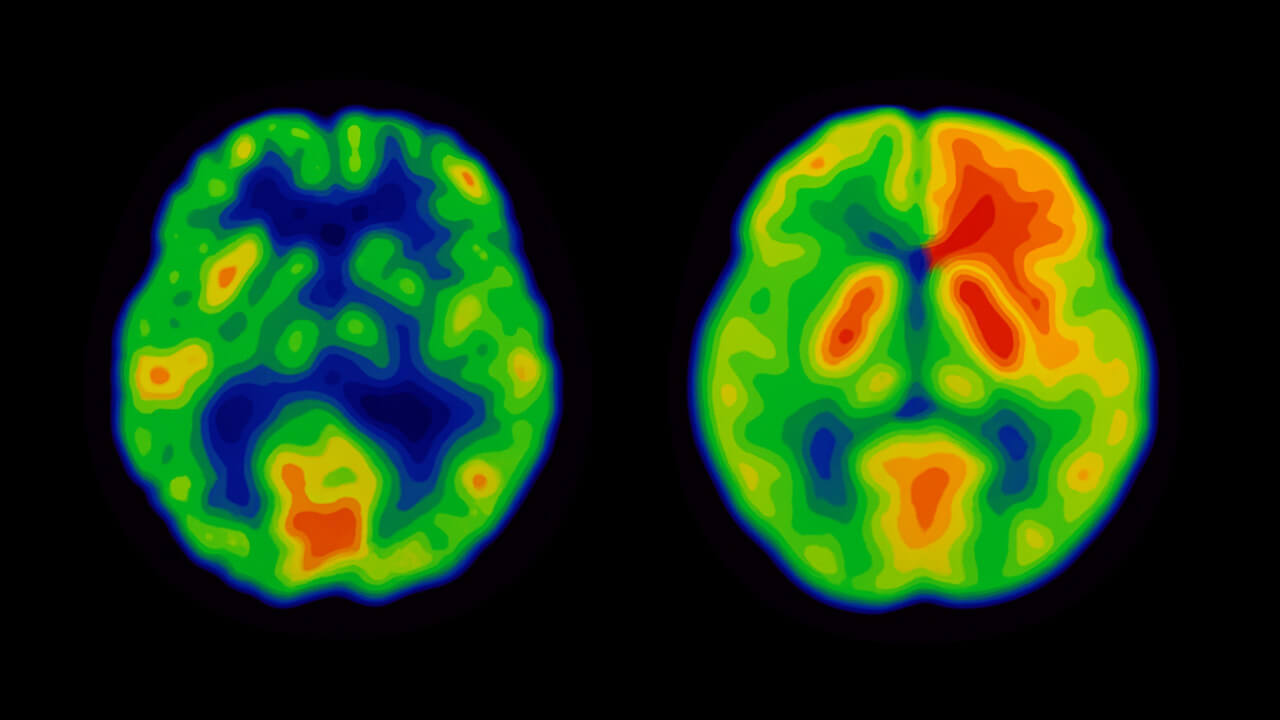

Because BHB can easily cross into the brain (given sufficient MCT1 transporter capacity), neuroprotective effects are also being discussed. Studies suggest possible benefits for neurodegenerative diseases such as Alzheimer’s, Parkinson’s, or dementia (e.g., Maalouf et al. 2007). However, these effects are still being researched and should not be taken as proven therapeutic claims.

Illustration (simplified): Improved brain energy supply via ketone bodies — even with insulin resistance.

Many users report noticeable mental clarity after taking ketone supplements, which could be linked to the anti-inflammatory and neuroprotective properties. Additionally, BHB demonstrably generates ATP more efficiently than glucose, which especially benefits the heart and brain (Veech 2004).